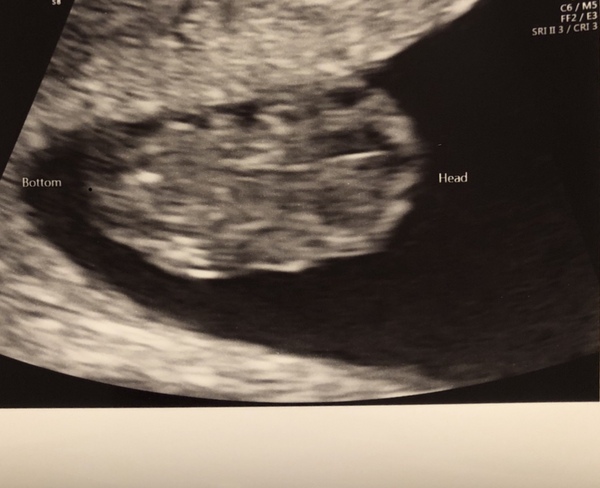

@Miniheart this was my scan at 9 weeks on the 10th of January! You can just about see its little arms and legs, we saw baby moving etc it was amazing!

Thank you for sharing this @Mae19 It must be so special when the scan goes well and you hear the heartbeat and get to see your little bubba!